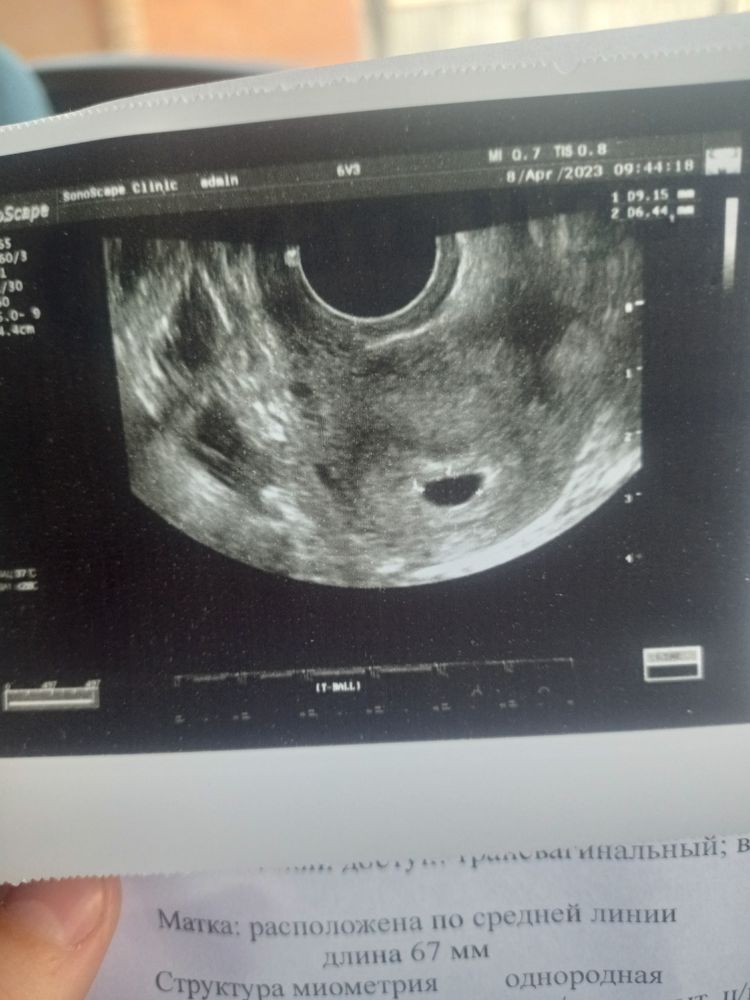

Сегодня были на первом узи. Беременность маточная, срок 4 недели и 5 дней. Плодное яйцо 8мм.

Теперь на узи через 14 дней и будем слушать сердечко. А потом